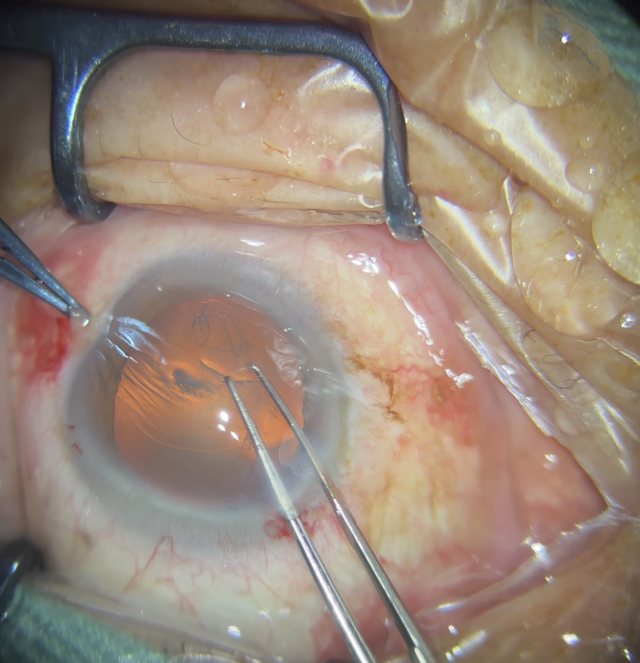

号外号外,湖南省人民医院副院长祖雄兵和眼科主任医师曾琦被指存在不正当关系,并有不雅视频传出。对此,医院工作人员回应:组织正在调查,请给医院宣传部门联系。当地卫生健康委员会对此回应:暂未接到相关的信访反映。祖雄兵为湖南省人民医院副院长,泌尿外科学科带头人。曾琦,博士,主任医师,硕士研究生导师。现任湖南省人民医院眼科副主任、眼科一病区主任,湖南省卫生健康高层次青年骨干人才,湖南省预防医学会眼病防治专业委员会主任委员、湖南省女医师协会眼科专业委员会主任委员、湖南省医学会眼科学专业委员会防盲学组副组长、湖南省医学会眼科学专业委员会眼外伤及职业病学组副组长、湖南省医学会眼科学专业委员会白内障学组副组长、